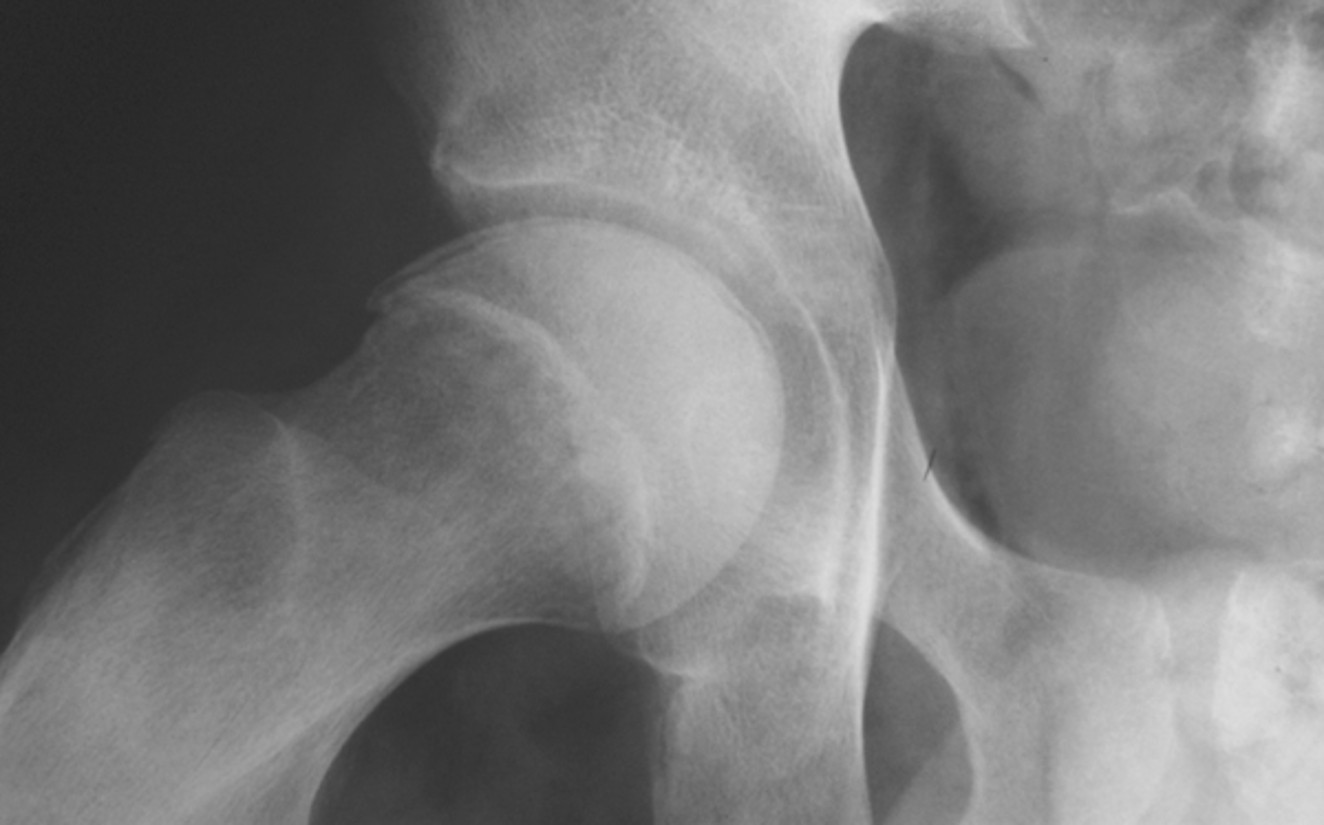

What is the hallmark radiographic sign of hip ischemic necrosis?

Crescent sign – subcortical radiolucent band representing a fracture line.

What does the Crescent sign indicate in avascular necrosis of the femoral head?

A crescent-shaped lucent subchondral fissure indicating a fracture line; seen best in abducted position.

What stage is this disease at?

Stage 4